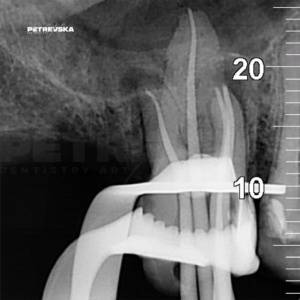

Пред before image

Потоа after image